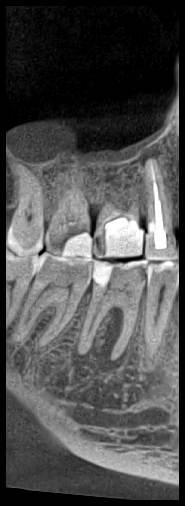

КТ от 04.03.2024

69273_3.jpg.f56a31dc1d8d53085767a9a52915128c.jpg69273_4.jpg.f9ec255bedbdb9fde8159318d3cb1fd9.jpg69273_5.jpg.36a7a942d403dd2eb062e5a4b2b58a52.jpg69273_6.jpg.492d3fbca3808fbdf58c86056b2fe0c3.jpg69273_7.jpg.f9bfdd5d593504dc7bd3710ece18aa4f.jpg69273_8.jpg.853e2342e6f2329a2e89c8939c2aad6f.jpg69273_11.jpg.e495813d50bf007f7165bf5f5dfec4b3.jpg69273_12.jpg.49b3cf66b4dd26b5cd68a91b2684e402.jpg69273_13.jpg.5d61b621b8e8b2c473ad6a8aca42502d.jpg